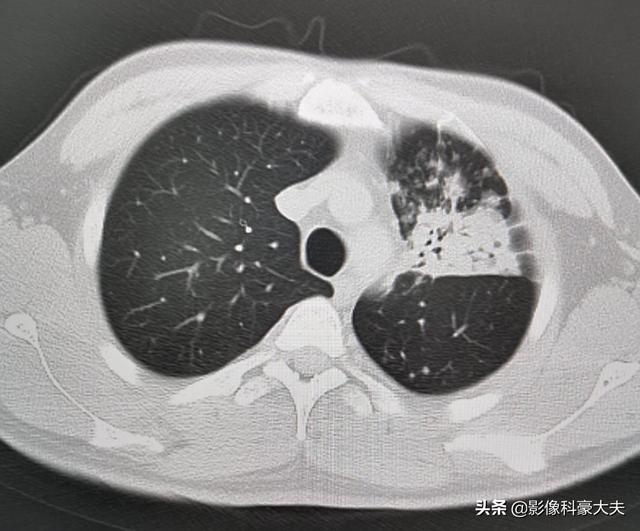

下の写真は、32歳で血糖値が30台だった患者がクレブシエラ菌に感染し、肺膿瘍、肝膿瘍、下肢感染症を引き起こしたものである:

左足は目に見えて腫れており、筋肉の隙間に黒い泡がたくさんある。このような重症感染症の患者は死亡率が高い!